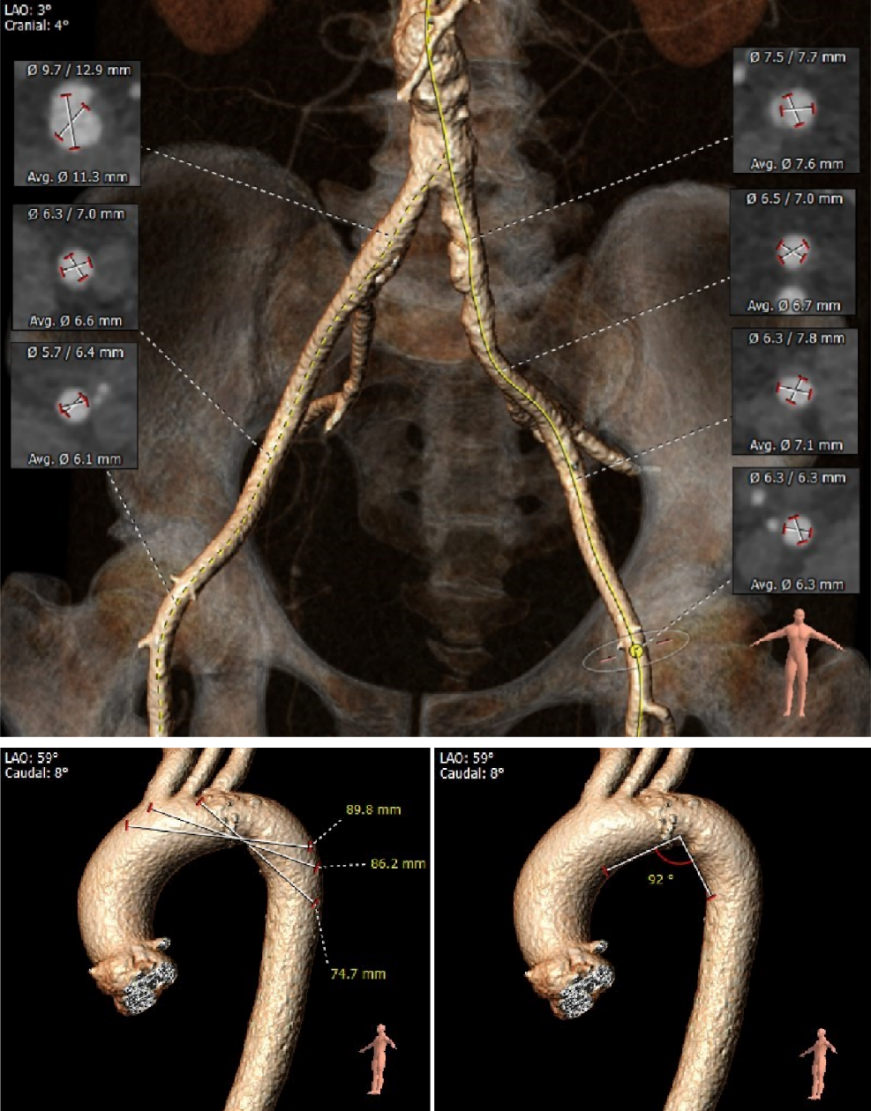

CT数据显示该患者为三叶式主动脉瓣。

1. 主动脉瓣瓣环周长77.0mm,平均周长径24.5mm,SOV:32.6mm*351.4mm*32.2mm,瓣叶增厚,瓣上钙化明显,HU850钙化积分913mm³。

2. 左冠开口高度18.8mm,右冠开口高度21.9mm,高度可,根据瓦氏窦内径和瓣叶长度综合判断,冠脉堵塞风险小。

外周血管及主动脉弓解剖

患者主动脉弓角度、弓距可。双侧血管内径可,未见明显钙化,股动脉分叉位置可,入路血管条件良好。